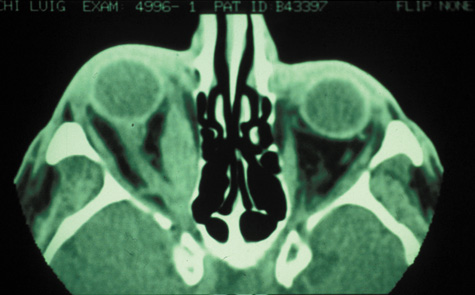

Computed tomographic findings in patients with both forms of the disease demonstrate areas that are almost metallic in density. These foci of irregularly calcified bone on CT may be pathognomonic (Fig. 22). On MRI, these areas appeared bright on T1-weighted imaging and have decreased signal on T2-weighted images, which may be related to the presence of ferromagnetic materials such as iron and manganese within the fungal concretions.115

Fig. 22. Aspergillosis. Computed tomography shows areas of extreme density of the ethmoidal bones.